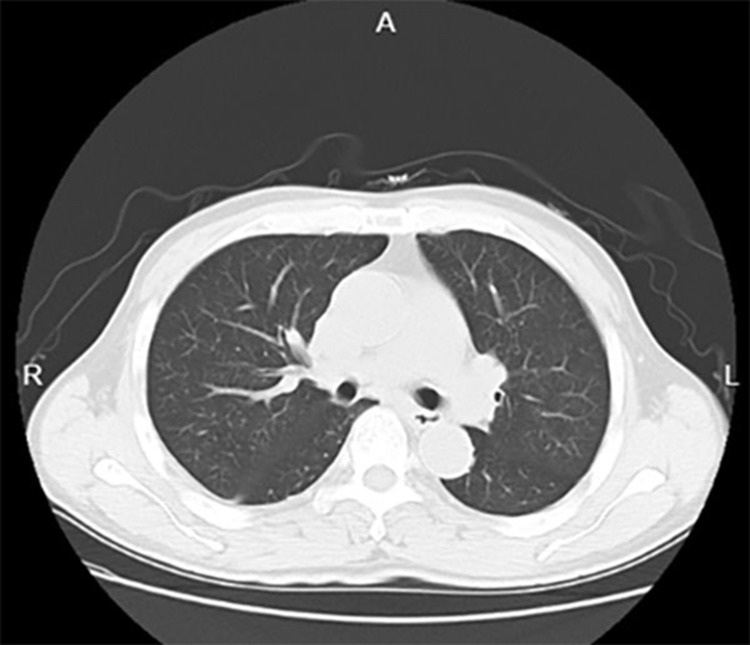

Case presentation: A 63-year-old male with a long-standing history of hepatitis B-related liver cirrhosis and a recent diagnosis of hepatocellular carcinoma presented with a rapidly enlarging painful right-sided thyroid mass associated with swelling but no systemic symptoms such as fever or dysphonia. This prompted a thorough diagnostic workup. Enhanced neck scans indicated a mass potentially originating from the thyroid with tracheal compression, yet crucially, there was no evidence of lung involvement based on the chest CT. Despite the rarity of liver-to-thyroid metastasis, the patient's multifaceted medical history warranted a broad differential diagnosis.